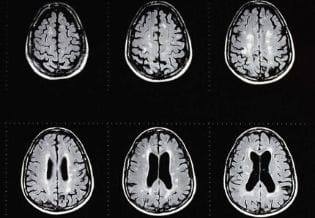

A year prior to this presentation, she was evaluated for blurred vision in her left eye. She had no previous medical problems then, nor did she have any family history of neurological disease. She was diagnosed at that time to have optic neuritis. Brain and total spine MRI’s were done at that time and demonstrated the presence of multiple lesions of demyelinating nature. These lesions were more consistent with Multiple Sclerosis. Visually evoked potentials and Somatosensory evoked potentials were also abnormal. Anti-Aquaporin 4 along and all the autoimmune work-up were negative. Lumbar puncture done at that time showed a high IgG index and the presence of oligoclonal bands. The patient received high doses of methylprednisolone intravenously with total resolution of the symptoms.

She was followed with brain and spine MRIs over several months after which she was considered to have a pediatric form of Mutiple Sclerosis. For this reason she was started on weekly intramuscular injections of interferon Beta 1a.